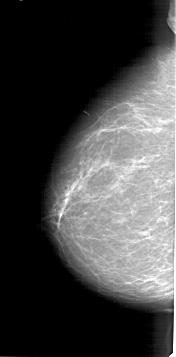

A_1403_1.LEFT_CC

LEFT_CC LINES 6421 PIXELS_PER_LINE 3166 BITS_PER_PIXEL 12 RESOLUTION 43.5 NON_OVERLAY